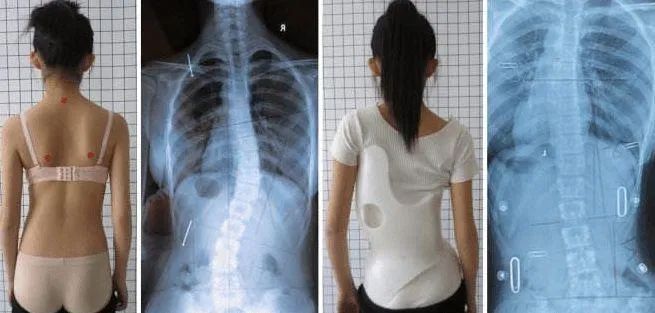

如果自測(cè)發(fā)現(xiàn)存在脊柱側(cè)彎的可能,請(qǐng)盡早前往醫(yī)院進(jìn)行診斷。滕州市中心人民醫(yī)院理療科門(mén)診設(shè)有脊柱側(cè)彎中醫(yī)藥干預(yù)門(mén)診,免費(fèi)為您提供篩查服務(wù),并根據(jù)每一位患者的側(cè)彎類型、程度和特點(diǎn),給予個(gè)性化專業(yè)矯正方案。通過(guò)理療、艾灸等中醫(yī)特色,結(jié)合運(yùn)動(dòng)康復(fù),幫助兒童青少年改善體態(tài),矯正脊柱側(cè)彎。